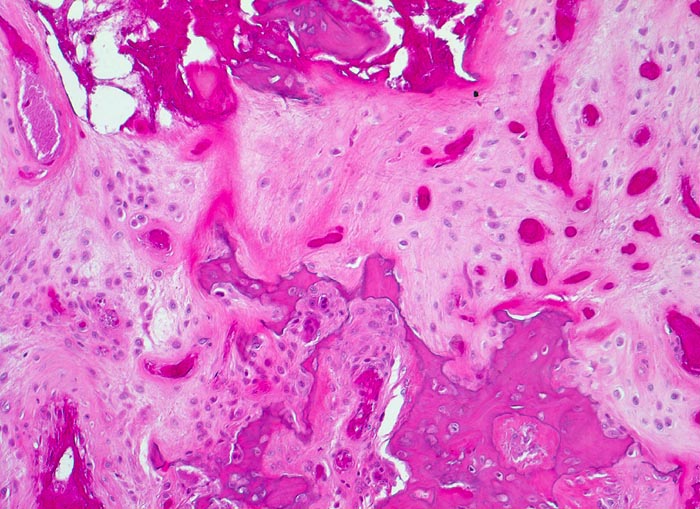

Makroskopisch ist die Nekrose im Anfangsstadium durch eine intensiv gelbe Verfärbung mit hämorrhagischem Randsaum charakterisiert. Häufig kommt es zur flächenhaften Ablösung des ansonsten intakten Gelenkknorpels (DD Arthrose!) zwischen subchondraler Knochenlamelle und angrenzender Spongiosa. In den Spätstadien sind die Nekrosezonen grau-gelb gefärbt und von körniger Konsistenz. Ein Teil der nekrotischen Spongiosabälkchen dient als Leitschiene für die Neubildung von Osteoid und mineralisierten Trabekeln, die an der Aussenseite angelagert werden. In der Nekrosezone kommt es zur Sequestrierung von Knochenbälkchen durch Frakturen. Die Markräume werden bindegewebig organisiert. In der Peripherie besteht initial ein hyperämischer Randsaum und im Verlauf kommt es zur Ausbildung einer metaplastischen Knorpel- und Knochenneubildung mit Randsklerose. Das Endstadium der Abräumreaktion untergegangener Knochenabschnitte stellt eine meist subchondral lokalisierte pseudozystische Umwandlung dar. Schliesslich kollabiert der Femurkopf und der Verlust der Gelenkkongruenz führt zu einer fortschreitenden sekundären Coxarthrose (> 3192)

• Flächenhafte Ablösung des gut erhaltenen Gelenkknorpels zwischen subchondraler Knochenlamelle und angrenzender nekrotischer Spongiosa.

• In der Nekrosezone osteoklastäre Resorption von avitalen sequestrierten Spongiosabälkchen.

• Ortsständiger Lamellenknochen wird als Leitschiene zur Fasernknochenneubildung benutzt.

• Pseudozystische Hohlräume in den nekrotischen Markräumen.

• Fibrosiertes Mark mit einzelnen thrombosierten Arterien.